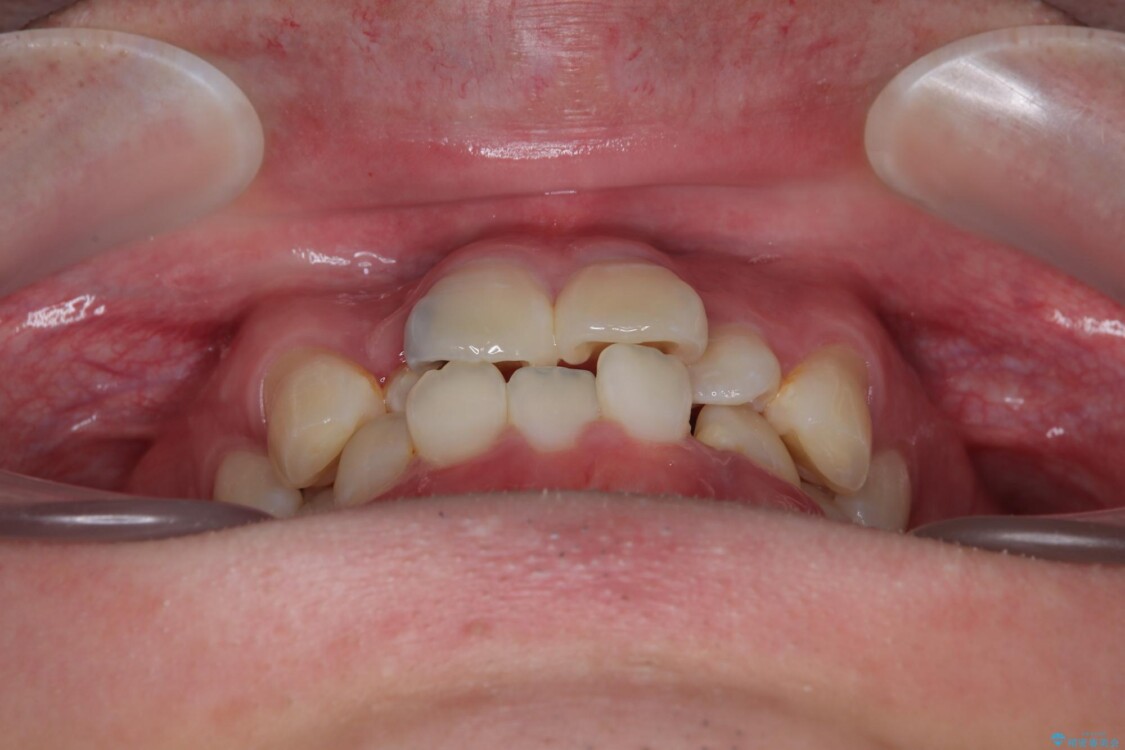

「歯並びがデコボコしていて、上下の中心がズレているのが気になる…」という悩みで来院された患者さまの症例をご紹介します。

・上下ともに歯がきれいに並びきらず、がたつきが見られました。

・上下の前歯の中心(正中)がずれています。

・特に上顎の幅が狭いため、下顎の歯列も内側に入り込み、歯が並ぶスペースが不足していました。

治療前